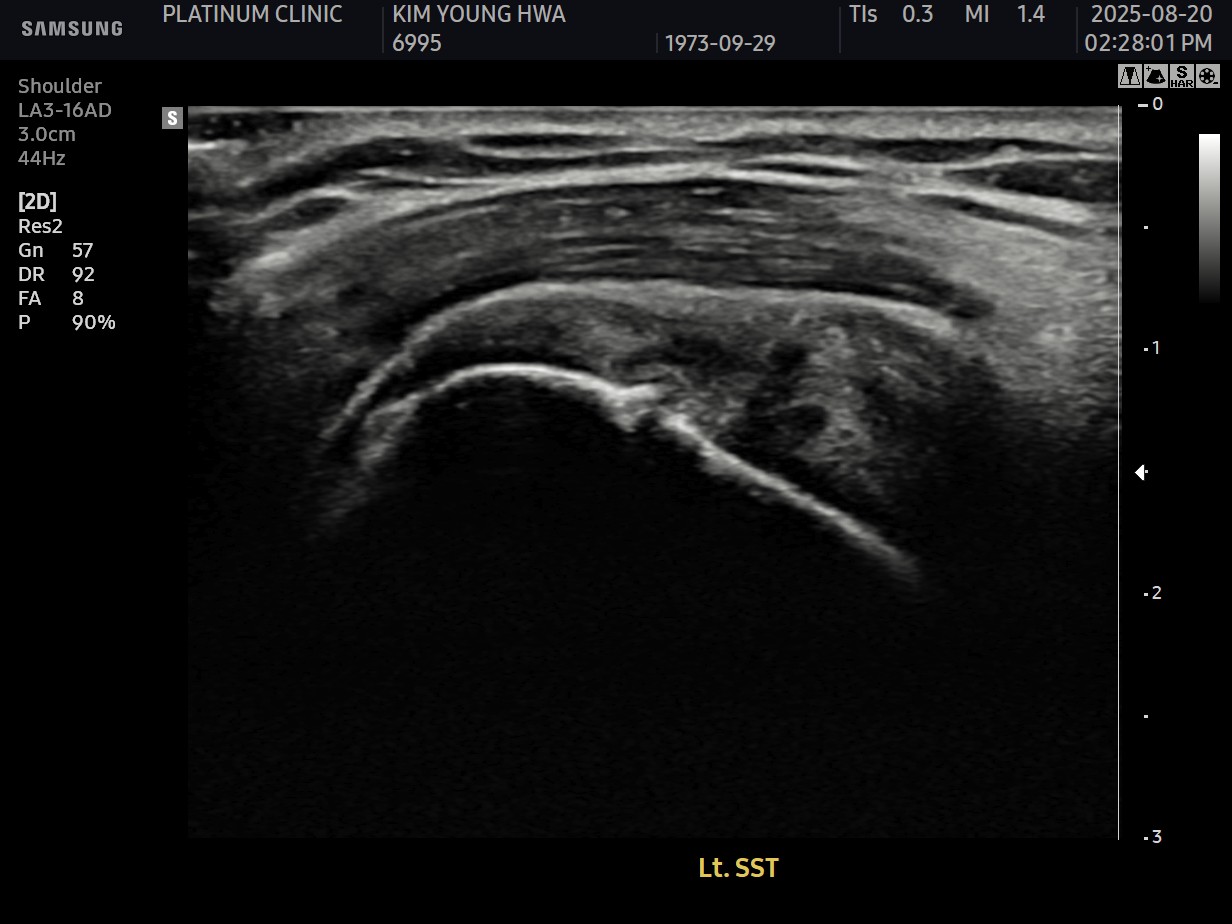

X-ray와 MRI, 초음파 검사를 시행했습니다.

진단 결과:

- ✓석회성건염: 극상건에 약 1.4cm 석회 (휴지기)

- ✓회전근개 관절면측 부분파열: 약 40%

두 가지 문제가 동시에 있었습니다.

시술 과정

시술 시간: 약 50분 (석회 제거 30분 + 봉합술 20분)